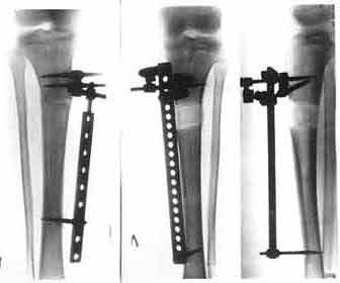

Before the

treatment.

After the